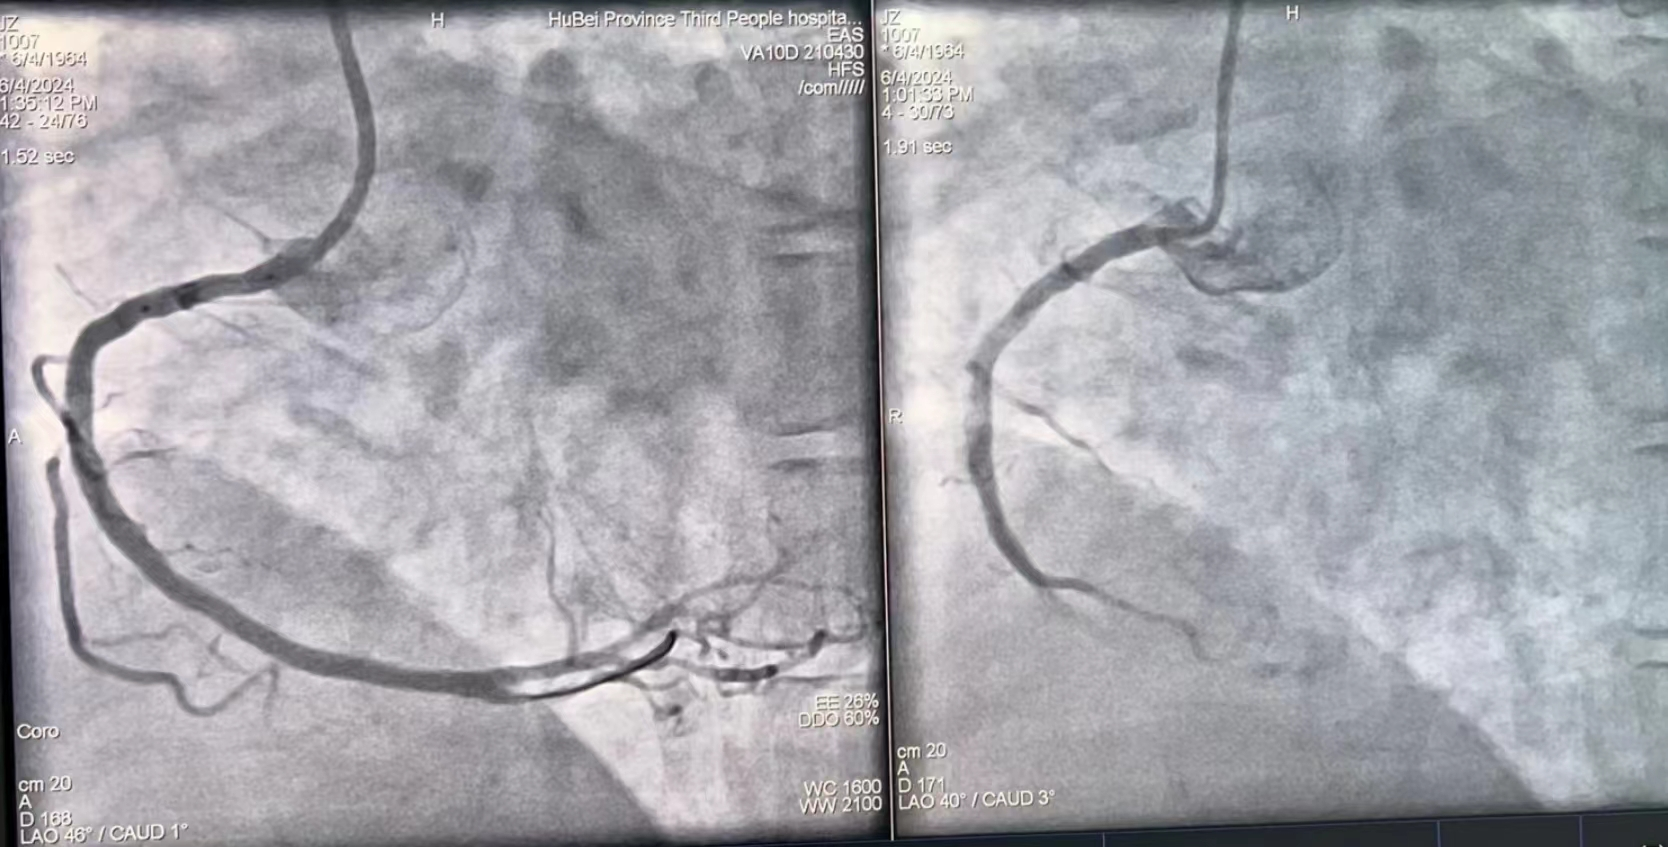

术后(左)与术前(右)对比

6月5日上午,夏爹爹外出购物,因天气炎热且购买物品太多,热得满头大汗、口干舌燥。到家后,他马上从冰箱中拿出一大瓶冷饮一饮而尽,酣畅淋漓之后,夏爹爹突感胸闷难耐,家人见状顿感不妙,急忙呼叫120送至湖北省第三人民医院(湖北省中山医院),行心电图检查后考虑急性心梗,心血管内科介入团队迅速启动,经胸痛绿色通道将夏爹爹直送导管室手术,半小时不到就开通了导致夏爹爹犯病的“犯罪”血管,把夏爹爹从死亡线上拉了回来。